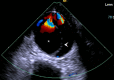

A man with sudden onset chest pain